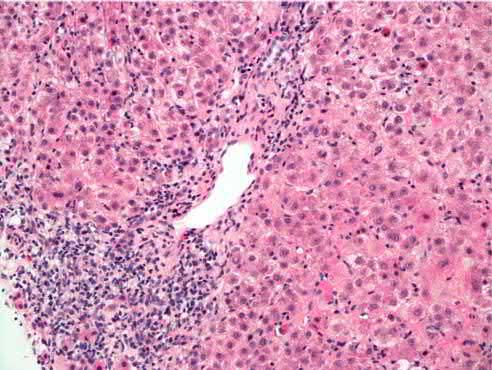

抛开特定抗体相关的AIH,单纯的狼疮性肝炎可能是存在的。这些肝损伤病人排除了AIH,而且还有抗核糖体P抗体检测常呈阳性,活检常发现汇管区周围淋巴细胞浸润伴孤立性坏死区域。但是,尚未确定抗核糖体P抗体的致病性。这让狼疮性肝炎充满了争议。

SLE患者的肝活检显示活动性界面性肝炎伴显著的门静脉淋巴浆细胞浸润,参考2